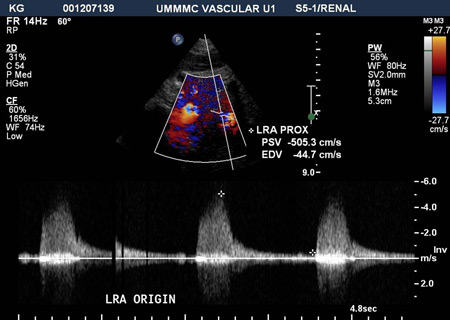

Renal Artery Doppler